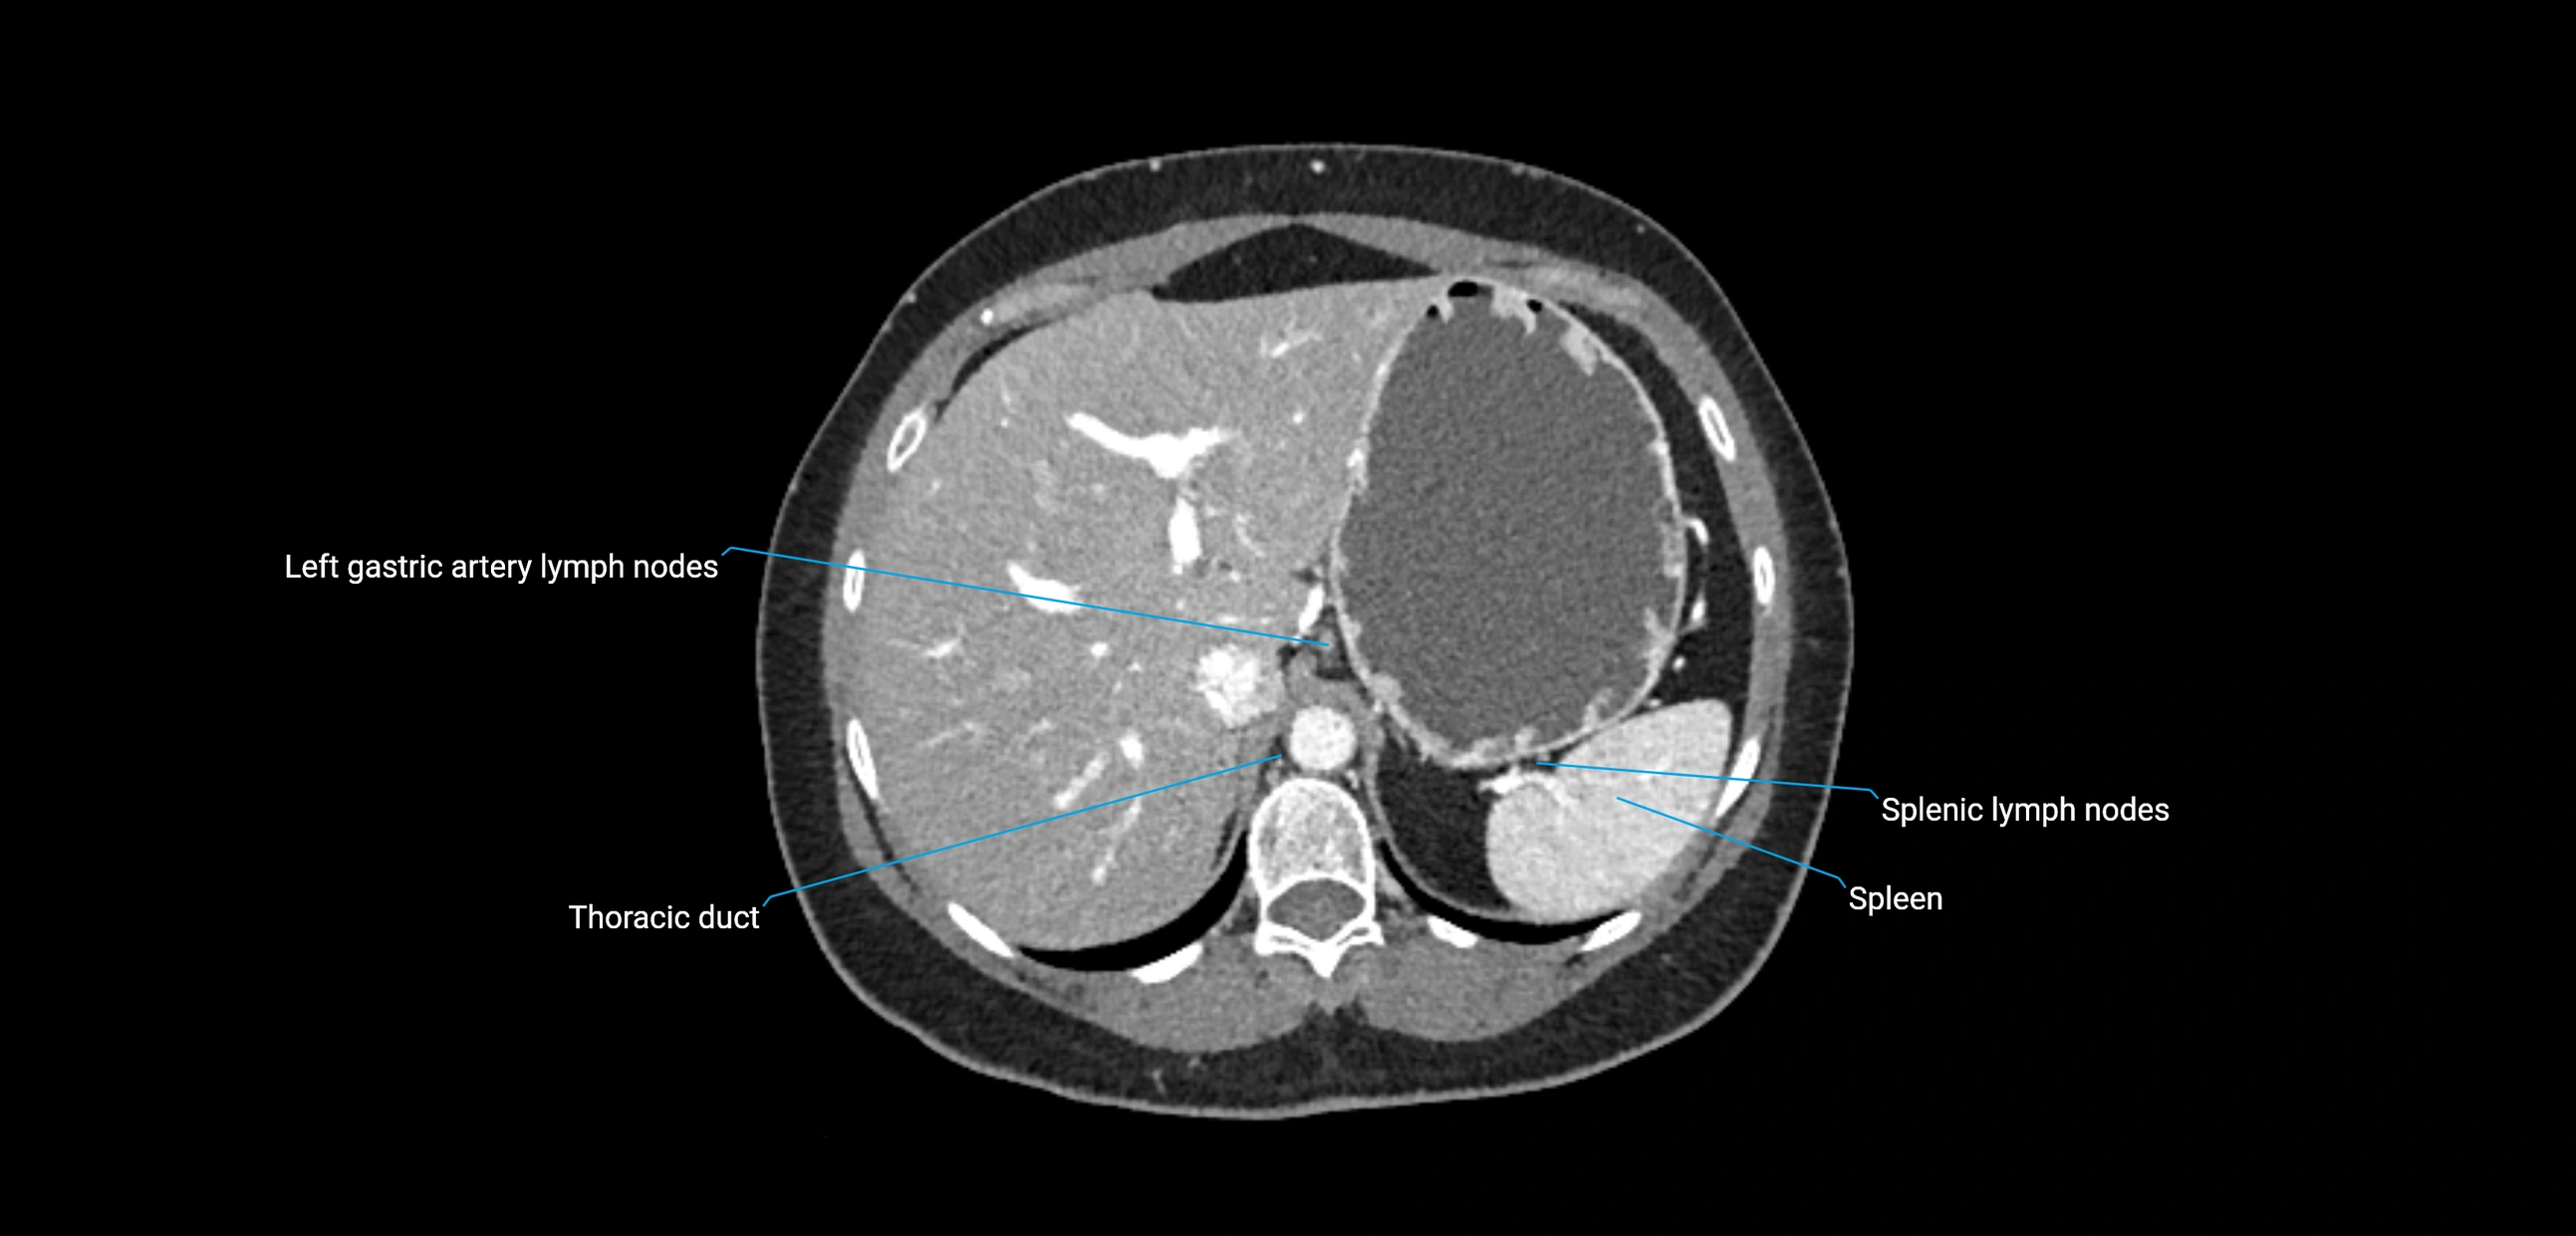

The lateral aortic lymph nodes (also called para-aortic lymph nodes) are a major group of retroperitoneal lymph nodes located along the abdominal aorta and its branches. They lie between the diaphragmatic crura superiorly and the bifurcation of the aorta at L4 inferiorly.

These nodes receive lymph from a wide range of abdominal and pelvic structures. Specifically, they drain lymph from the kidneys, suprarenal glands, gonads (testes/ovaries), uterus, uterine tubes, and pelvic organs, before converging into the lumbar lymphatic trunks, which terminate in the cisterna chyli → thoracic duct.

CT Appearance

CT Post-Contrast:

• Normal nodes enhance homogeneously

• Malignant nodes may show heterogeneous enhancement, central necrosis, or conglomerate formation

• Size >1 cm short axis is suspicious, though morphology and distribution are equally important